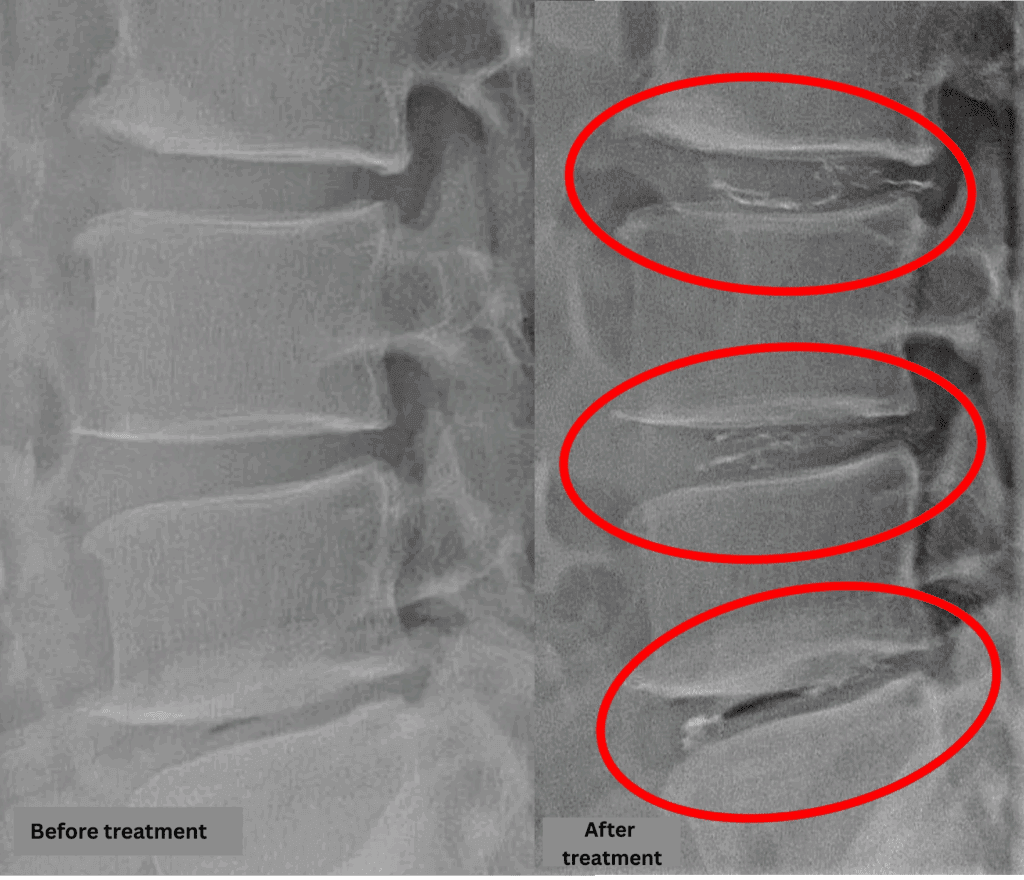

- L2/3, L3/4, L4/5 – Disc degeneration, disc herniation

The above findings were also observed on the imaging.

Findings show that compression of the spinal canal on discs L2/3, L3/4, and L4/5 is likely to be the cause of symptoms.

After consulting with the patient, the Cellgel Method was performed on L2/3, 3/4 and 4/5.